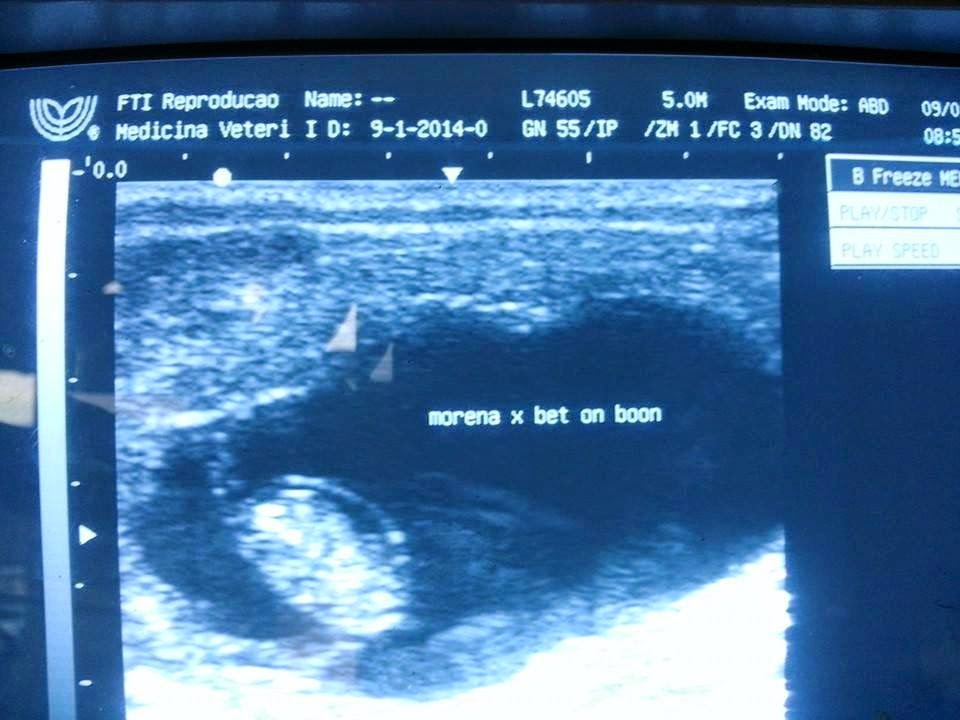

- Serviço de prenhes

- Diagnóstico de gestação